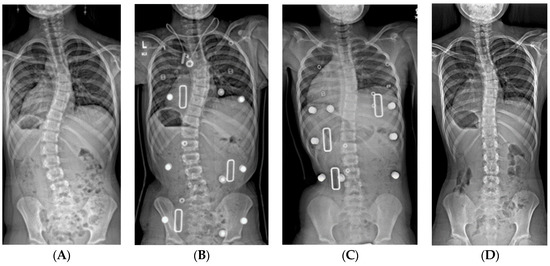

Figure 3.

(A) 19-month-old male with PWS deletion type with 52° curve. (B) Same patient at 20 months old, sitting in his first spinal cast, 10° curve in cast. (C) Same patient at 35 months old, after completing 8 casts, 11° curve. (D) Same patient at 6 years old, 3 years out of cast and 2 years out of brace, with an 18° curve.

Oore et al. reported the only published series of serial casting for children with PWS, noting a reduction of curve size in their ten patients, from 45° to 37° [40]. We reviewed our results from 34 children with PWS with more than 24 months’ follow-up after their initial spine cast. The average age at initial casting was 32 months (range 14–64 months) with an average of 8 casts (range 3–18). Twelve children (35%) were in the “cured” group; all were weaned out of brace at one year after completion of casting. Seven of these patients had maternal disomy 15, five had the 15q11-q13 deletion, and the average initial curve was 44° (range 27°–80°). Another 18 patients transitioned to long-term brace wear (10 with deletion, 7 with maternal disomy 15, and one having an imprinting defect). Their average initial curve of 55° (range 27°–84°) became 35° (16°–64°) at the end of casting and was 46° (27°–84°) at two years’ follow-up. Four patients with severe initial curves (54°, 84°, 95°, and 106°) were controlled in casts until they reached a sufficient age for surgery (average 56 months old). Overall, the odds ratio for “curing” an initial curve of <50° was nine times that of a curve >50° in this cohort.